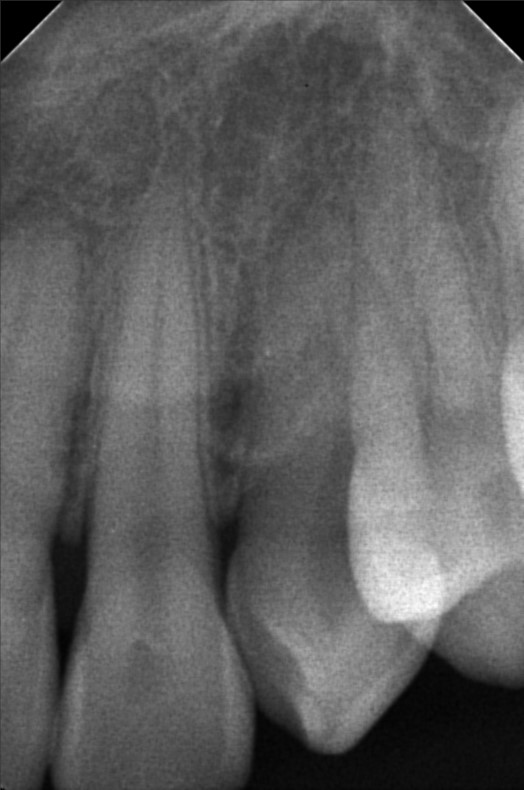

Edit Record Check our patient data records. Add patient information Patient Info Profile picture Last Name First Name Middle Name Birthdate Age Street Barangay City Country Zip Code Contact number Email Procedure 06/30/23- Informed Consent Ortho Check Up OP Impression Soft tissue analysis Intraoral photograph PA Radiograph For exo #15 Informed pt regarding class 5 cases Referred for cephalometric radiograph For resto class 5 #23, #24, #25, #35, #13, #14 10/24/25 oral prophylaxis xray tooth extraction #15 for restoration: abrasion: #23, 24, 25, 26, 14, 33, 35, 36, 44 recession: #13, 12, 11, 21, 22, 34, 32, 43 File atecotech2i712f_f.jpeg File 2 atecotech2i18f6_f.jpeg File 3 atecotech2i2a08_f.jpeg File 4 atecotech2i6330_f.jpeg File 5 atecotech2i278f_f.jpeg File 6 atecotech2i5dba_f.jpeg File 7 File 8 File 9 File 10 File 11 File 12 File 13 File 14 File 15 File 16 File 17 File 18 File 19 File 20 Retain Record Retain Record Yes No Save Your Changes